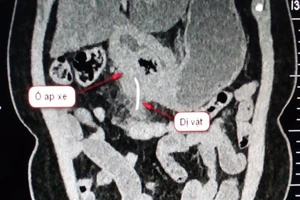

#BV Quận 11 Đau Âm Ỉ Nuốt Xương Cá Phẫu Thuật Suýt Thủng Dạ Dày

Nuốt tọt xương cá dài 5 cm vô bụng mà không biết